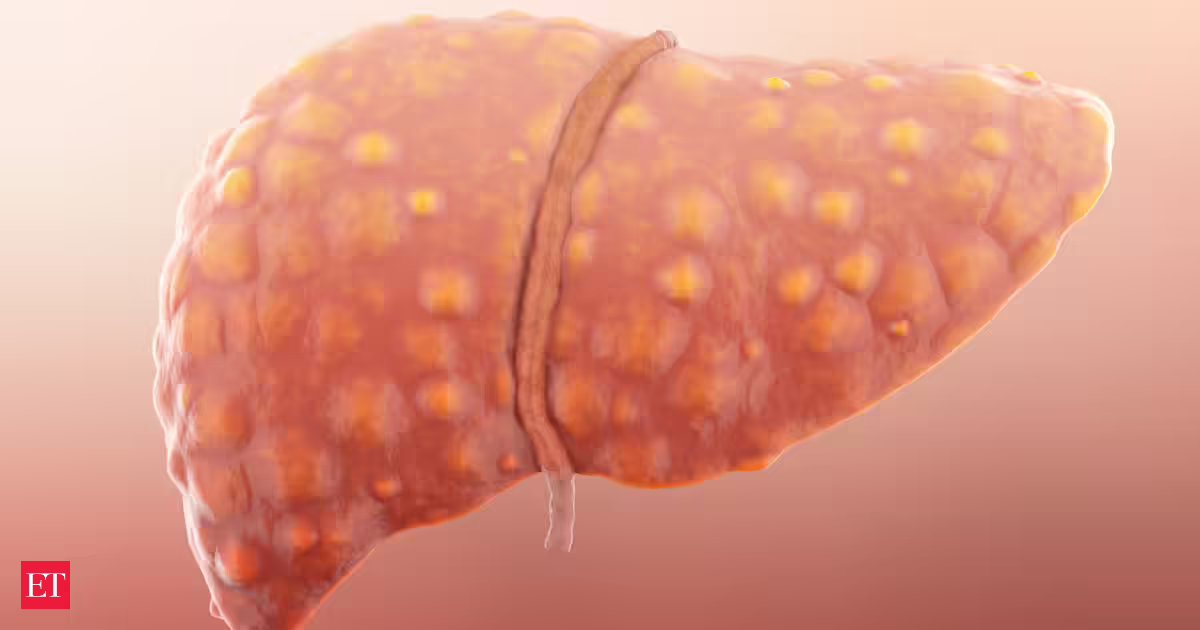

Aumento do risco de cirrose hepática e câncer de fígado

Apesar destas melhorias, os especialistas alertam que o número crescente de casos de MASLD representa um risco a longo prazo. Um grande número de pacientes aumenta o risco de complicações graves, como cirrose hepática e câncer de fígado no futuro.